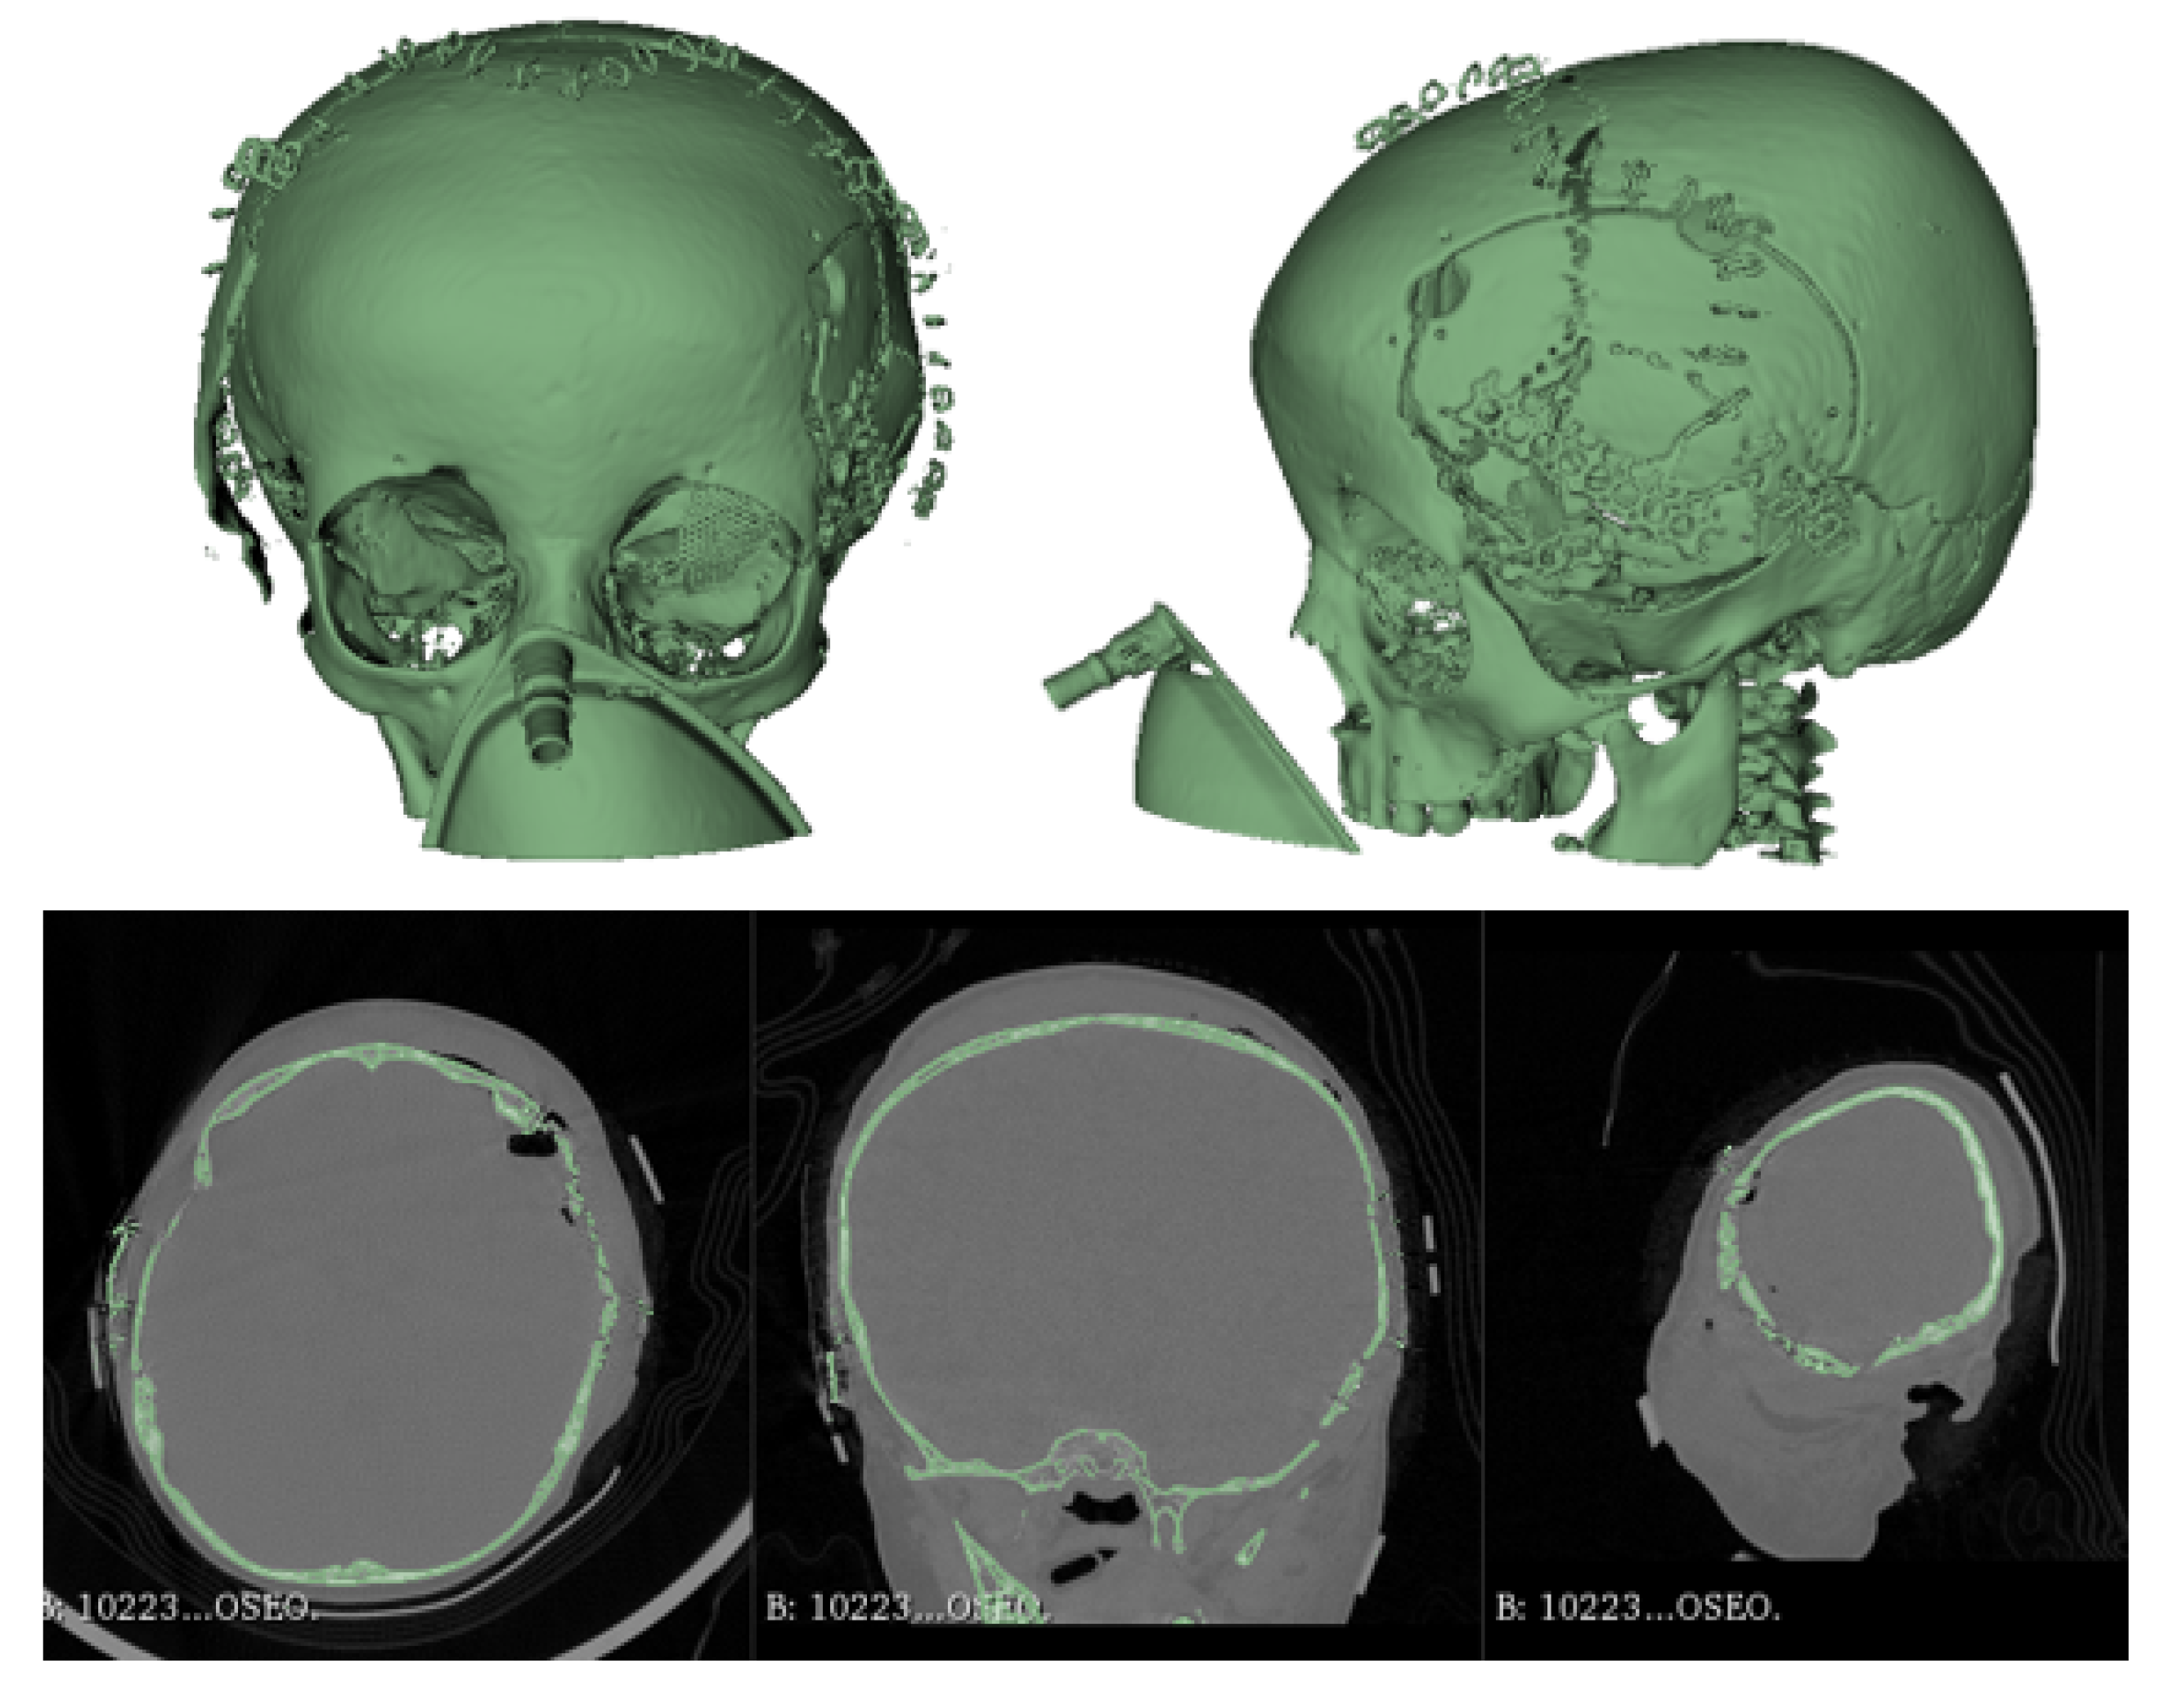

3.7.3. Design and Printing of Anatomical Models

3.7.4. Intraoperative Approach

3.7.5. Post-Operative Results